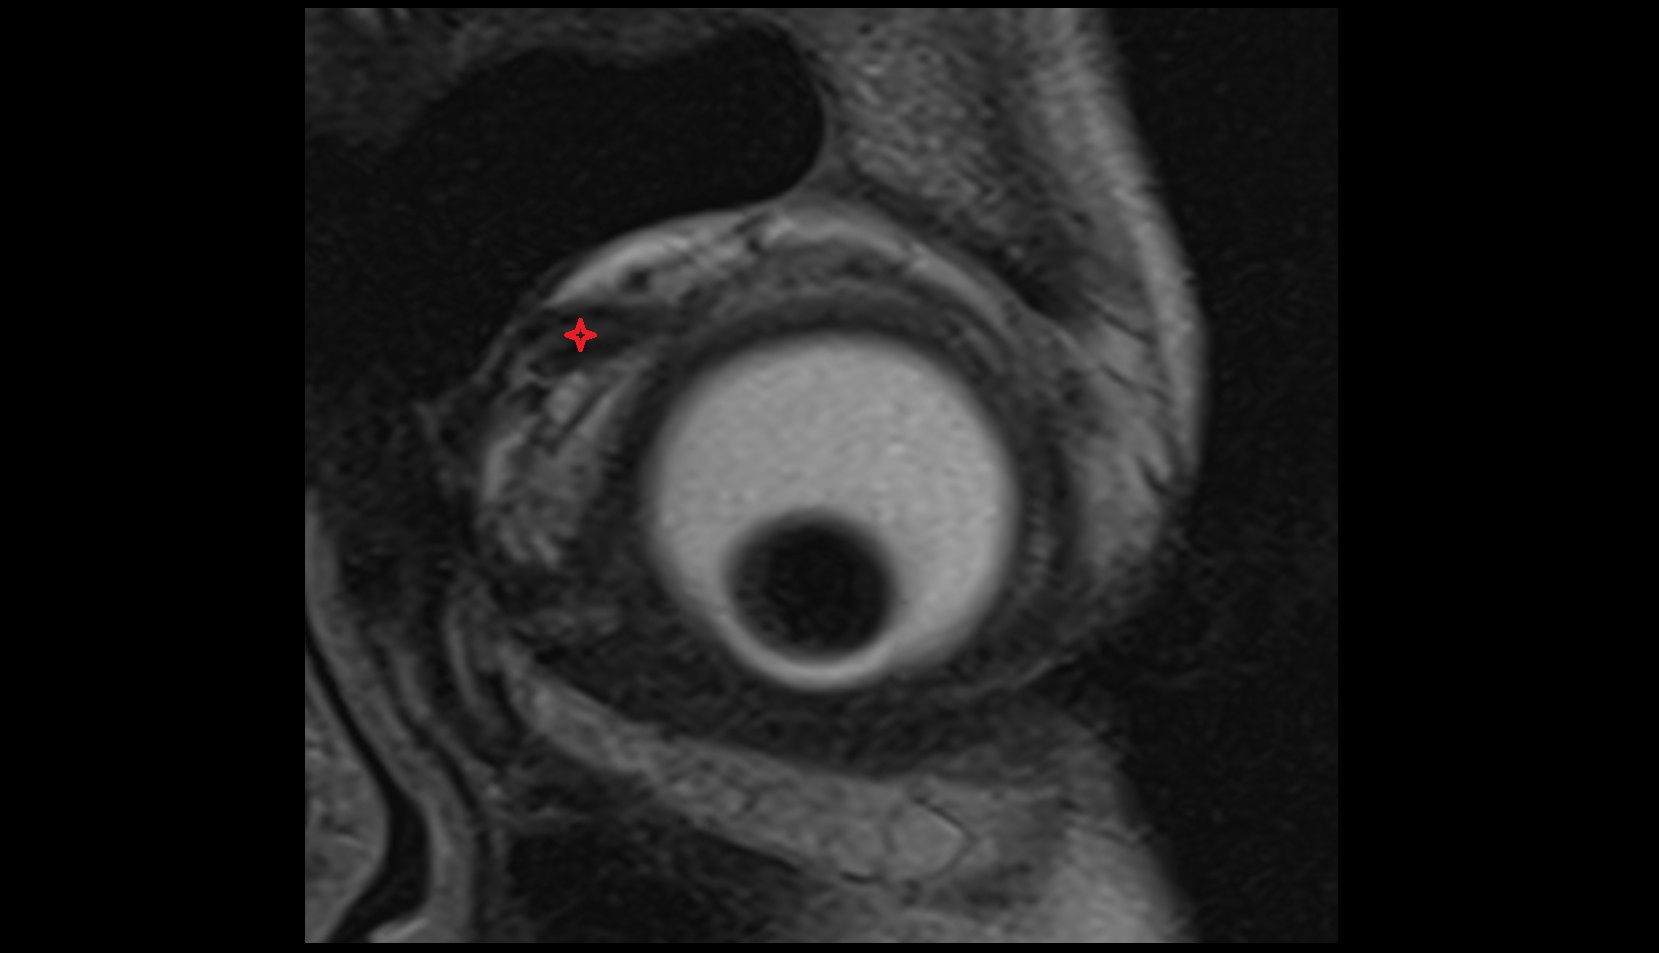

- Peripheral zone of prostate

- Anterior Fibromuscular Stroma of prostate

- Central zone of prostate

- Transitional zone of prostate